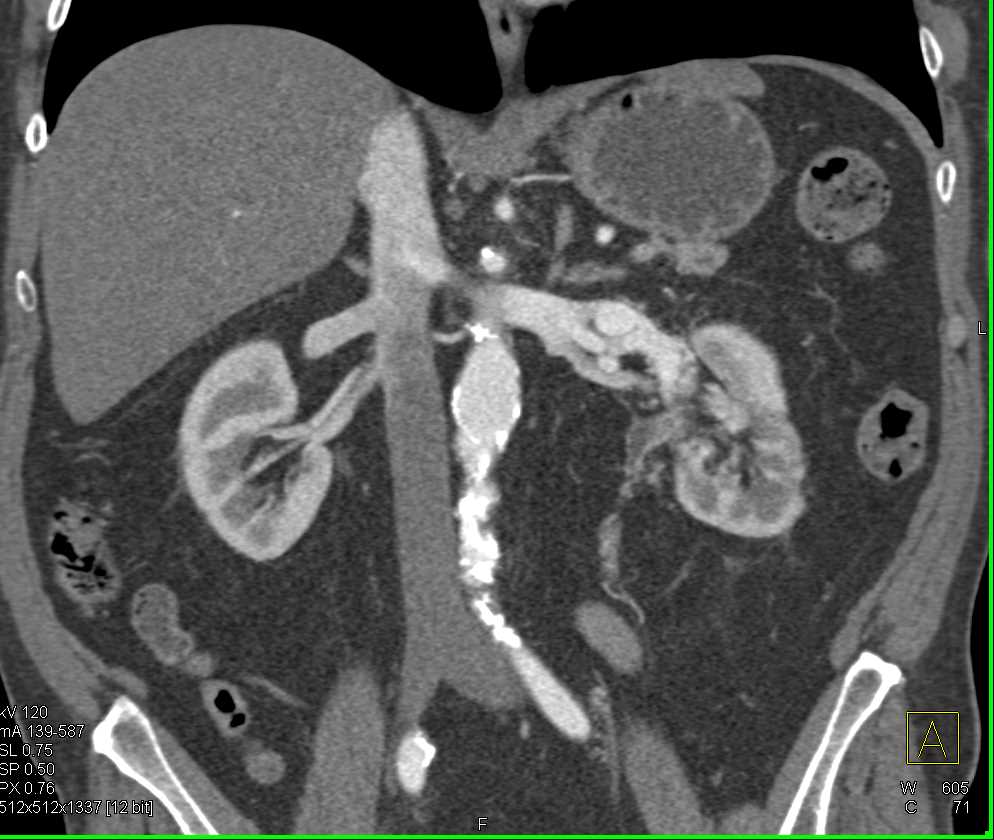

Tumor Encases the Aorta